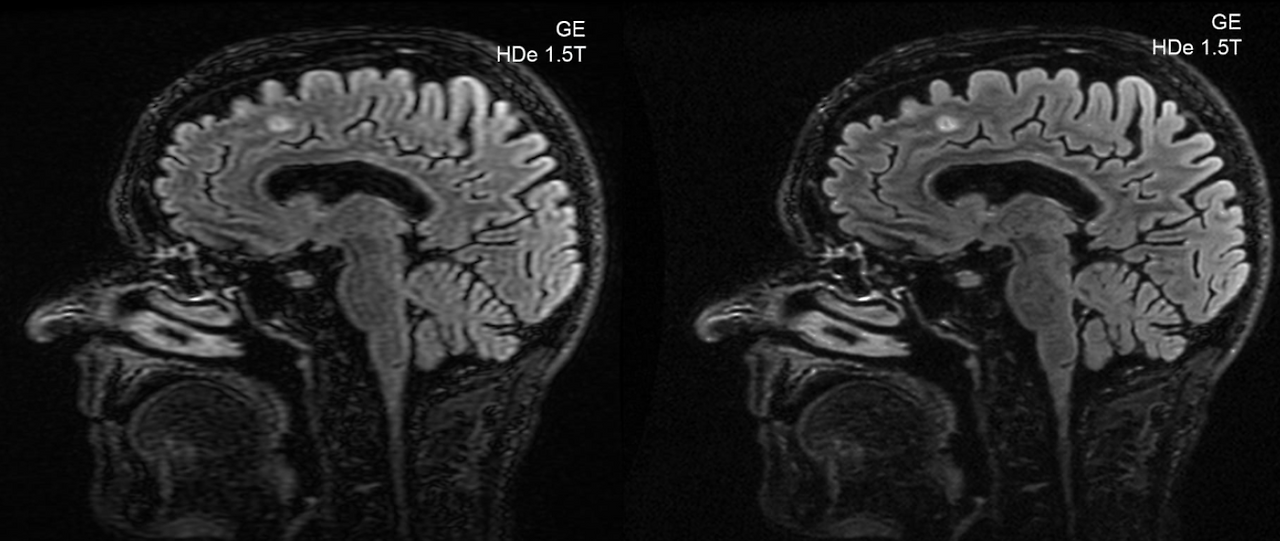

medical2.png 의료 영상 복원 예시

SR 기술은 근본적으로 영상의 퀄리티를 복원하는 곳에 사용됩니다. 범죄 수사에서 희미하게 찍힌 범인의 얼굴을 복원하여 몽타주를 작성하거나 잘 보이지 않는 자동차 번호판을 복원하는 데에 사용됩니다. 또는 MRI 등의 의료 영상이나 보안, 관제 등에 활용될 수 있습니다. 특히 해상도에 따라 가격이 급증하는 열화상 분야나 저해상도의 옛날 영상을 시청할 때도 유용한 기술입니다.